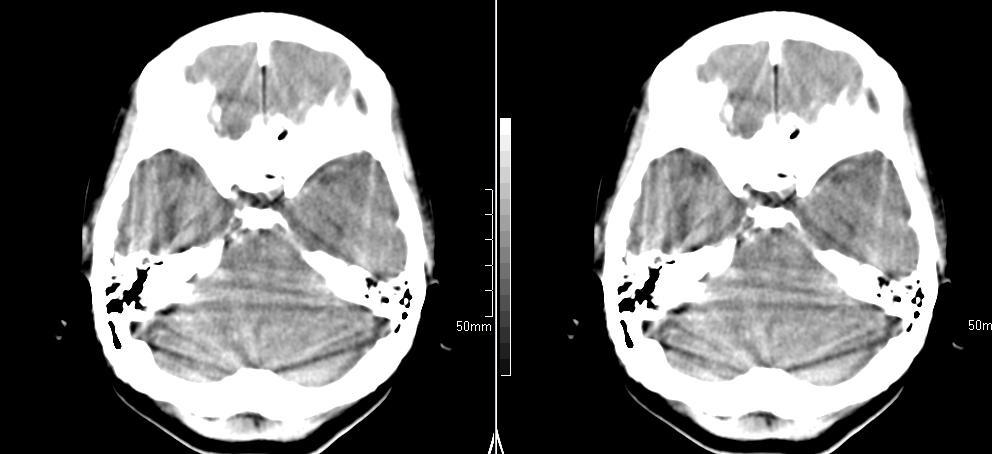

标题: CT23966:女,34岁,近一月头痛、意识障碍 [打印本页]

标题: CT23966:女,34岁,近一月头痛、意识障碍

左侧额叶见不规则软组织影,部分囊变,病变略呈等密度,占位效应明显,考虑血母可能。脑膜瘤不除外

左侧额叶肿瘤样病变,成等密度,其内可见囊变,肿瘤似与大脑镰相连,周围水肿不明显。考虑脑膜瘤可能!建议强化或mri。

左额叶囊实性肿块,实性部分呈等密度,密度不均,考虑胶质瘤可能性大,脑膜瘤及室管膜瘤不除外,建议mri增强扫描。

左额叶较大等低混杂密度影,占位效应明显,首先考虑:左额叶胶质瘤。